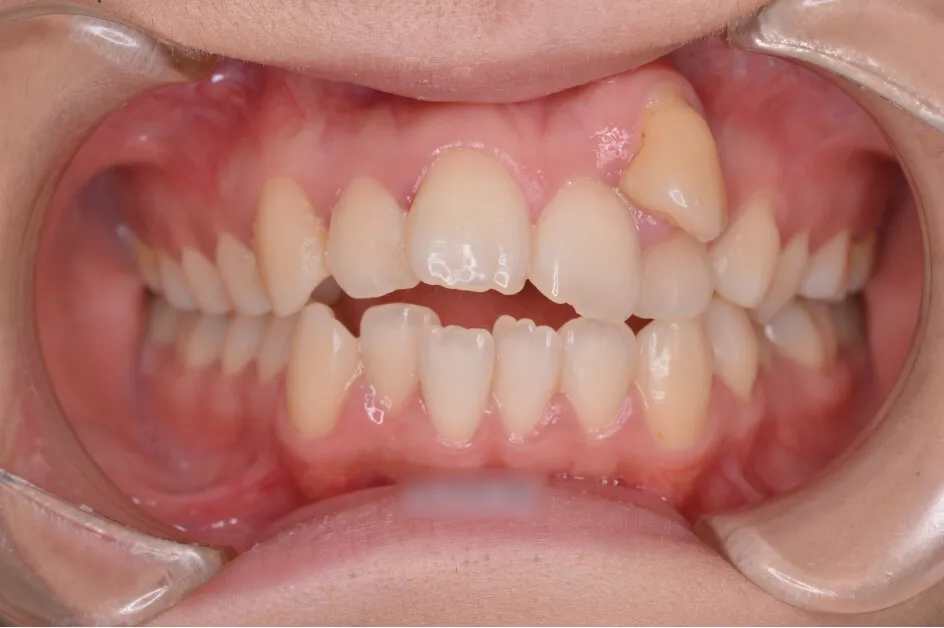

左上の糸切り歯が完全に歯列に並びました。

開咬状態も改善されてきました。